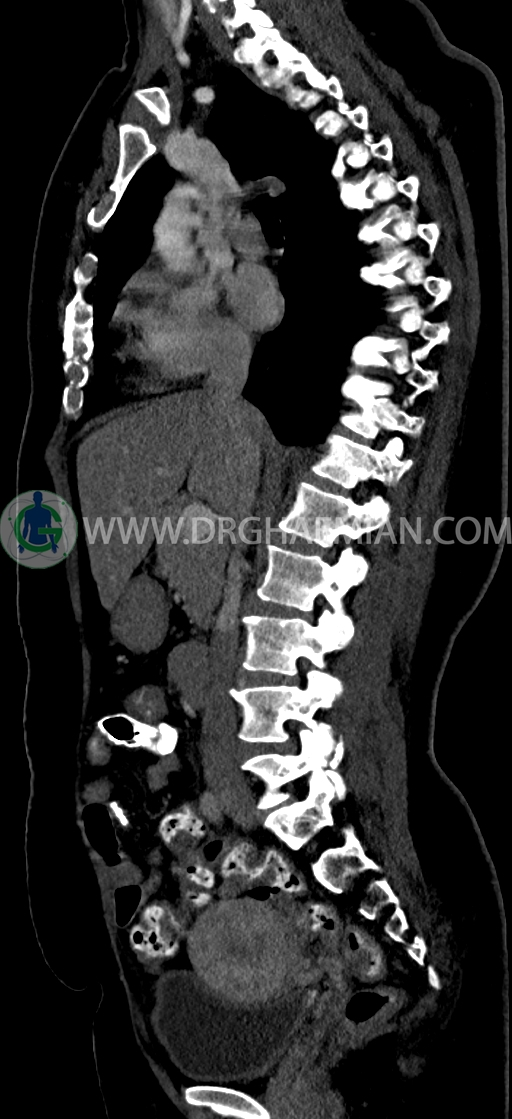

در سي تي اسکن اسپيرال ريه و مدياستن-شکم و لگن با کنتراست خوراکی و وريدی (مولتي ديدکتور 16 با مقاطع ظريف و بازسازي هاي ساژيتال و کرونال) :

–Bridging osteophyte در مهره هاي توراسيک مطرح کننده DISH همراه با کيفوز مشهود است.

-افزايش ضخامت منتشر محيطي کولون عرضي، که مي تواند در زمينه کوليت باشد.

– Retroaortic left renal با اتصال در محل مناسب به IVC